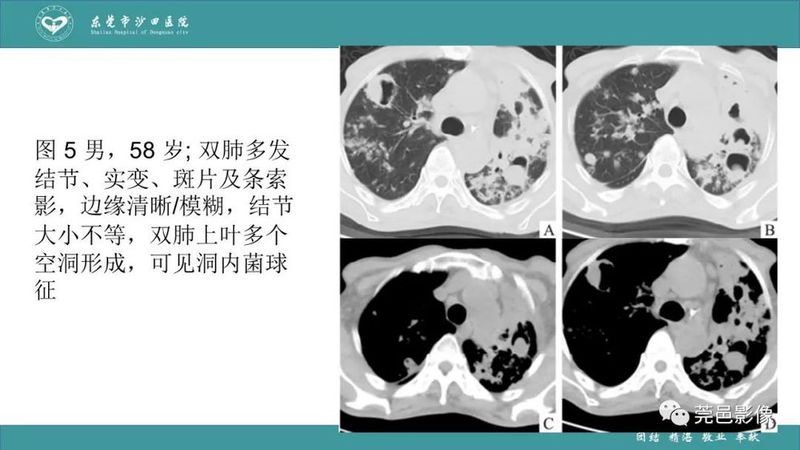

「肺炎克雷伯杆菌肺炎」影像学诊断+鉴别诊断